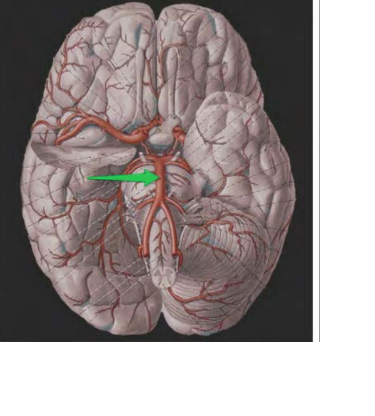

a. carotis int. sin.

chiasma opticum

a. basilaris

pons

crus cerebri Dex.

Crus cerebri sin.

hypophysis

tractus olfactorius dex.

bulbus olfactorius